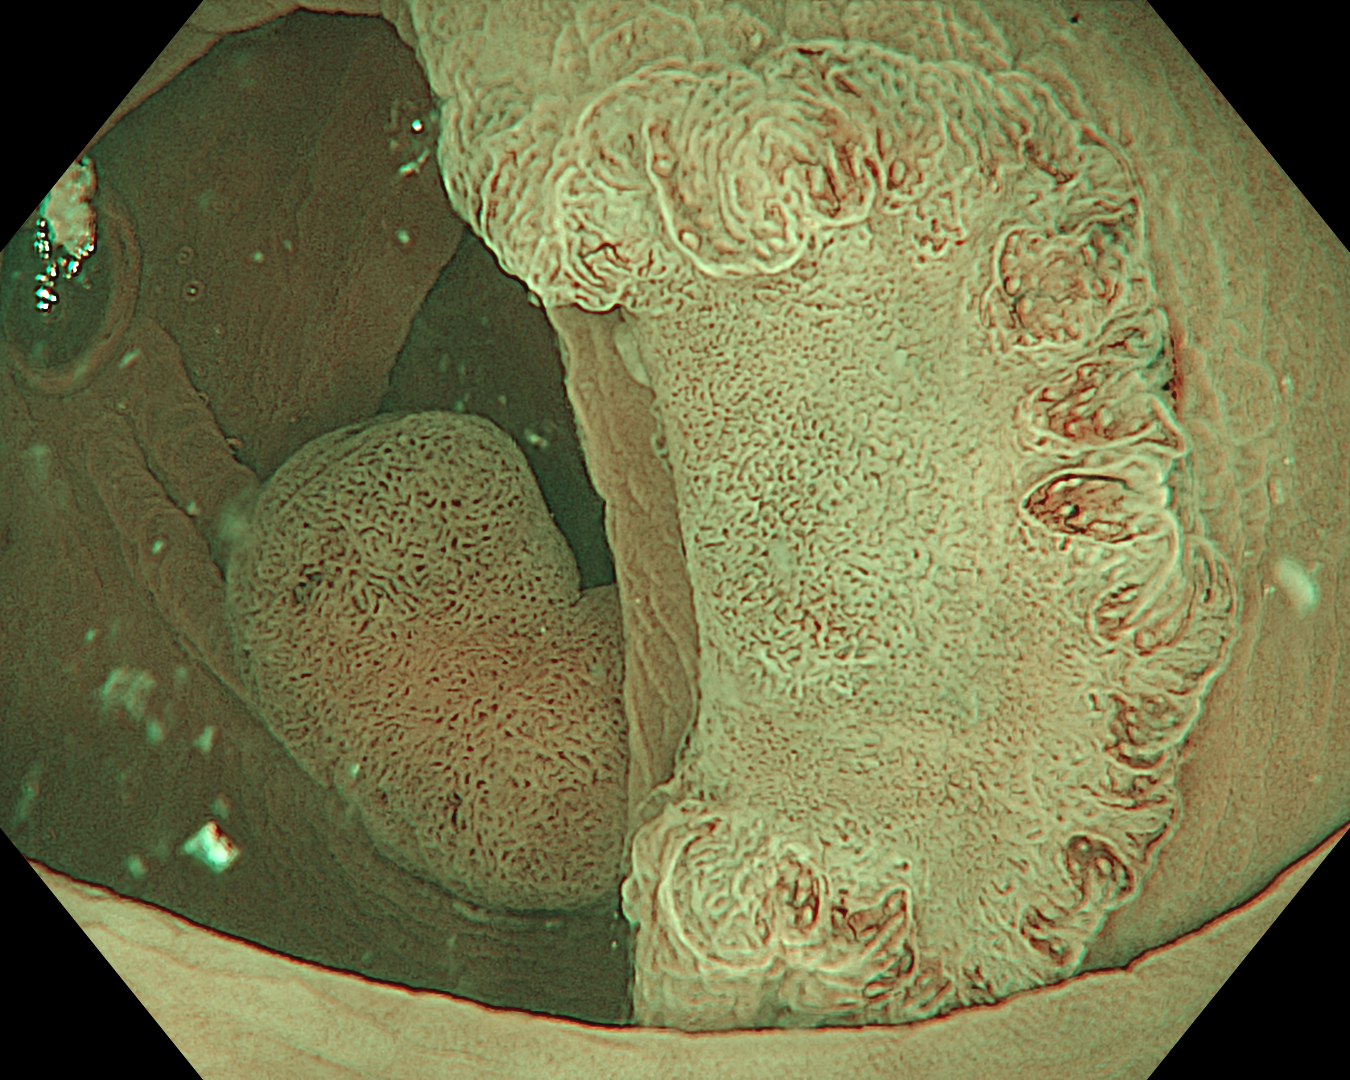

9. Underwater observation

Underwater observation in NBI mode. It appears that the lesion has the consistency of sclerosis in both size and shape.

10. Underwater observation

Underwater, we can easily observe the entire lesion with enhanced imaging modes.

11. Underwater observation

12. Underwater observation

Underwater, we can easily observe the entire lesion with enhanced imaging modes. TXI mode 2 is similar to white light but enhances the visualization of mucosal surfaces, helping to evaluate surface patterns and vessel patterns better than white light, so the images are more familiar to use.

This was an LST-NG-PD-type mucosal cancer in the transverse colon. By using image enhancement modes (WLI, TXI, and NBI with or without magnification mode), surface and vessel abnormalities of the lesion are clearly observed, making an important contribution to the assessment and classification of the lesion. Underwater observation, visualization of the entire lesion is easier, while assessment of surface pattern and vessel pattern of the lesion is still very clear.

This is a LST-NG-PD with a 16-mm diameter. The lesion has a red O-ring with a depressed area about 14mm in diameter. In “air” endoscopy and underwater endoscopy, the lesion has a “non-extension” or “sclerosis of the wall” sign. Observing in the “near focus” magnifying endoscopy, some areas had JNET type 2b, suggesting that this is either an intramucosal cancer lesion or a cancer lesion with submucosal invasion.